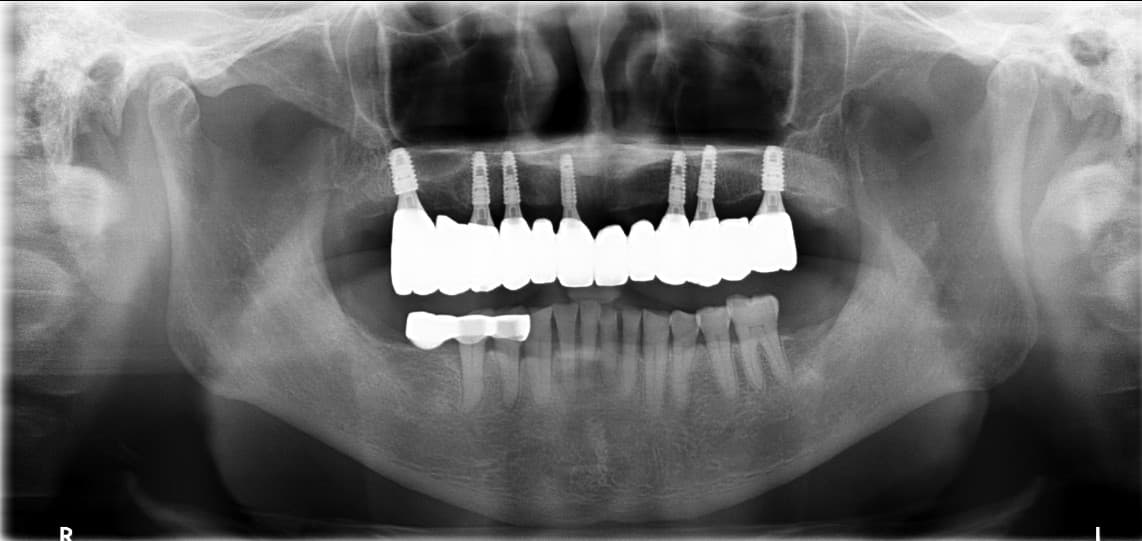

To'liq implant

oldin va keyin

Haqiqiy bemorlarimizning ajoyib o'zgarishlarini ko'ring

After ✨

Kim●● · 60 yoshdan oshgan erkak

Yuqori jag to'liq implant